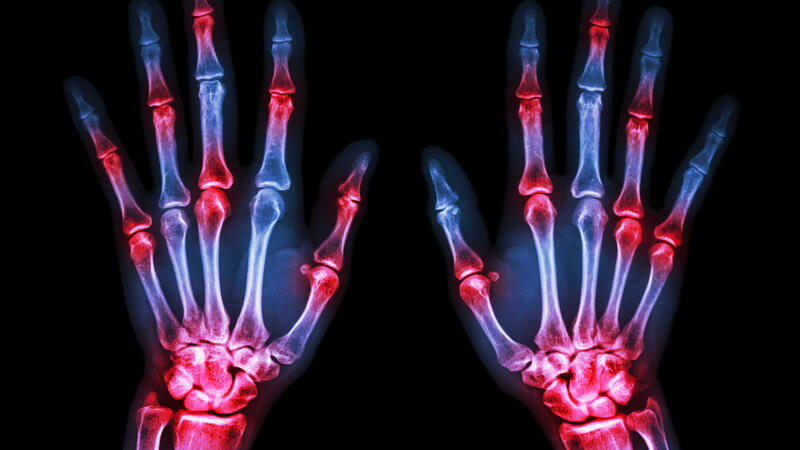

Rheumatoid arthritis (RA) affects the synovial membrane encapsulating the joints and causes swelling, which may, in turn, cause severe joint pain and deformity. The study, which involved 82 participants, confirms that both palm and finger temperature increase significantly in patients with Rheumatoid Arthritis and this makes the thermal camera an important diagnostic tool.

Rheumatoid Arthritis affects more than 400,000 adults in the UK which can lead to deformity, disability, and cardiovascular problems. Although timely detection of arthritis through continuous ultrasound is very important to help detect the disease, it's impractical and costly.